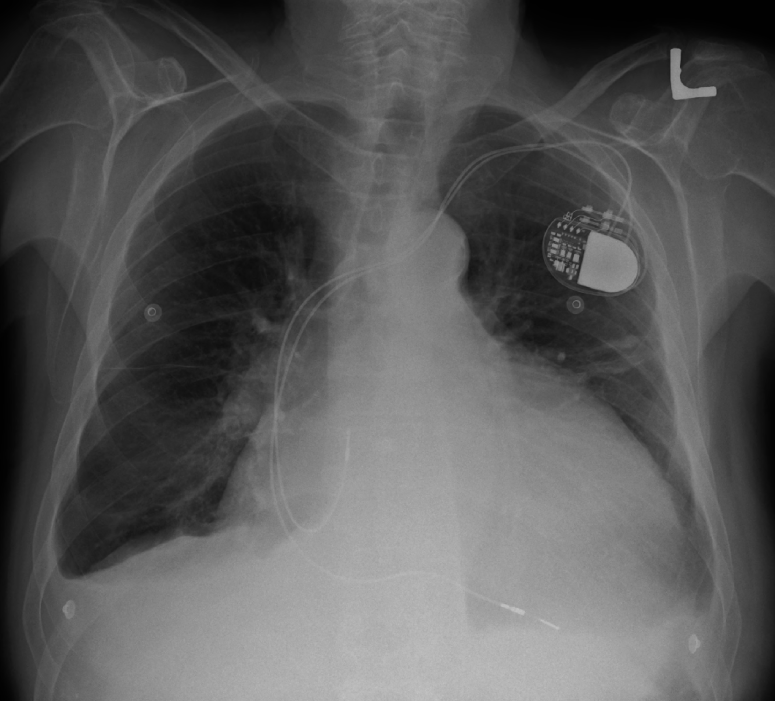

Cardiomegaly means that your heart is larger than normal. Often, it is a term used to describe the heart’s appearance on a chest X-ray.

If the heart appears to be large on the chest X-ray, then a transthoracic echocardiogram is often the next best test to look at the heart size, structure, and function to see if there is a problem.